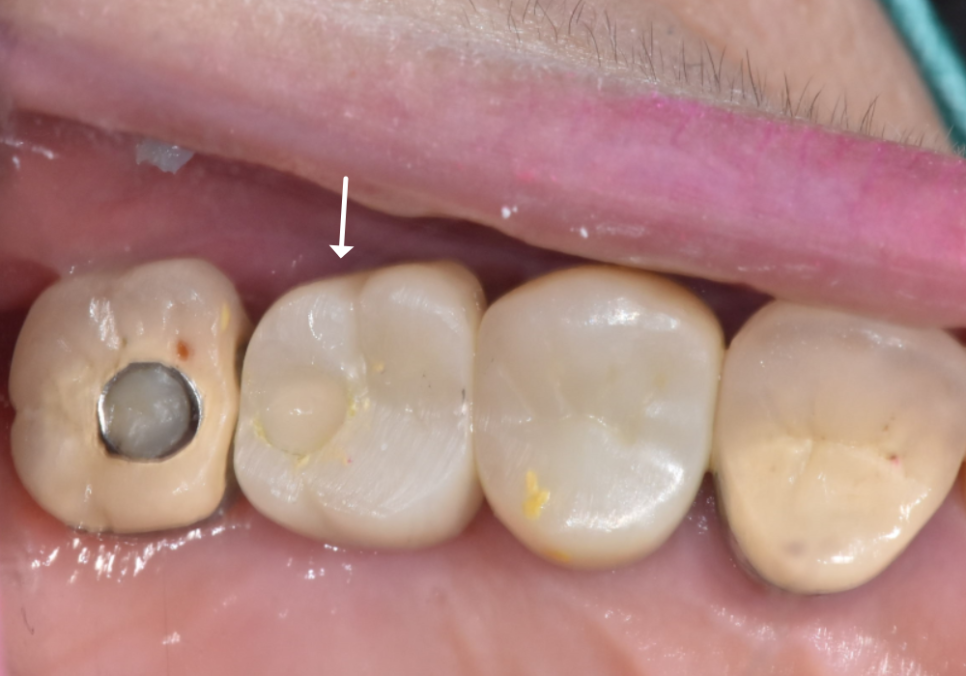

결과는? 다행히 파절 없이 깔끔하게 분리 성공!

문제 된 임플란트만 쏙 골라 안전하게 제거했습니다

240429

최종적으로 강도가 우수한

'지르코니아' 보철물을 올려드리며

모든 치료를 마무리했습니다.